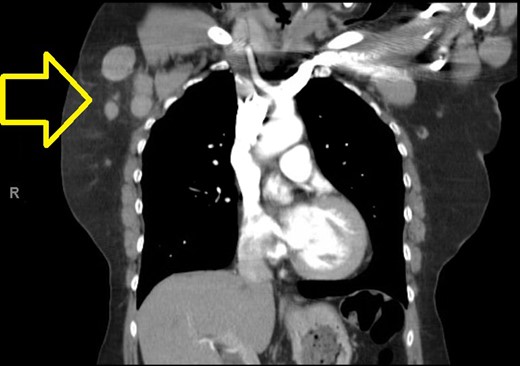

A computed tomographic (CT) scan of her chest with contrast revealed moderate right axillary lymphadenopathy and a lesion in the upper outer quadrant of the right breast measuring 1.3 × 1.2 cm (Fig. 1). A positron emission tomography (PET) scan showed a small intense focus on the right lateral breast consistent with carcinoma, significant right axillary lymphadenopathy and intense fluorodeoxyglucose hypermetabolic activity consistent with metastatic spread. Additionally, enlarged lymph nodes extending along the upper chest wall just inferior to the subclavian vessels and posterior to the pectoralis muscles were seen. A needle biopsy of the mass revealed an extensive involvement of poorly differentiated infiltrating carcinoma (Fig. 2). The tumor showed large nuclei with eosinophilic cytoplasm and prominent nucleoli consistent with apocrine differentiation (Fig. 3). There was a significant inflammatory response to the infiltrating tumor noted. No lymphovascular invasion was identified within the core biopsies. The specimen was estrogen and PR negative as well as HER-2/neu negative.

Chest CT showing lesion in the right breast and moderate right axillary lymphadenopathy.